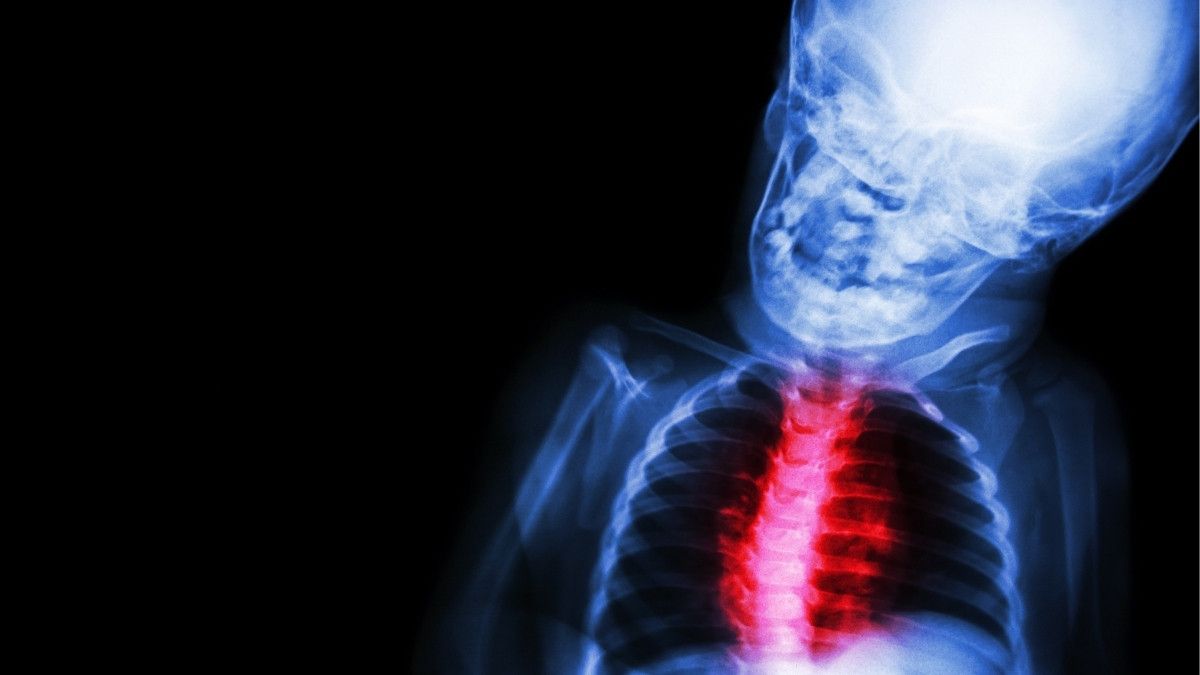

Penyakit jantung bawaan dapat didiagnosis sejak bayi masih berada di dalam kandungan. Menurut dr. Astrid Wulan Kusumoastuti penyebab penyakit jantung bawaan (PJB) pada janin belum diketahui pasti.

“Ada beberapa faktor risiko kehamilan yang meningkatkan risiko PJB pada bayi. Misalnya, adanya riwayat PJB di keluarga atau riwayat sindrom genetik pada keluarga, ibu menderita diabetes tidak terkontrol, riwayat infeksi virus pada kehamilan seperti TORCH termasuk rubella” kata dr. Astrid.

“Terpapar toksin (zat atau racun) tertentu, konsumsi obat-obatan tertentu selama hamil juga bisa meningkatkan risiko janin mengidap PJB,” tambahnya.

Berikut penjelasan lebih lengkap mengenai penyebab penyakit jantung bawaan pada janin.